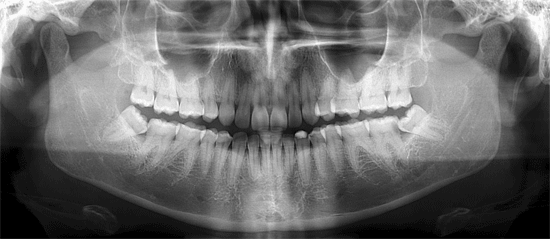

Ortho X - Radiografia Panorâmica

Tem uma ampla cobertura da área examinada com menor dose de radiação quando comparada ao levantamento periapical. É indicada para grandes áreas patológicas, problemas de ATM, desvio de sépto nasal, extrações de 3o. molares, verificações de crescimento e desenvolvimento na ortodôntia e odontopediatria, fraturas de mandíbula, para diagnóstico geral inicial e preservações de tratamentos.